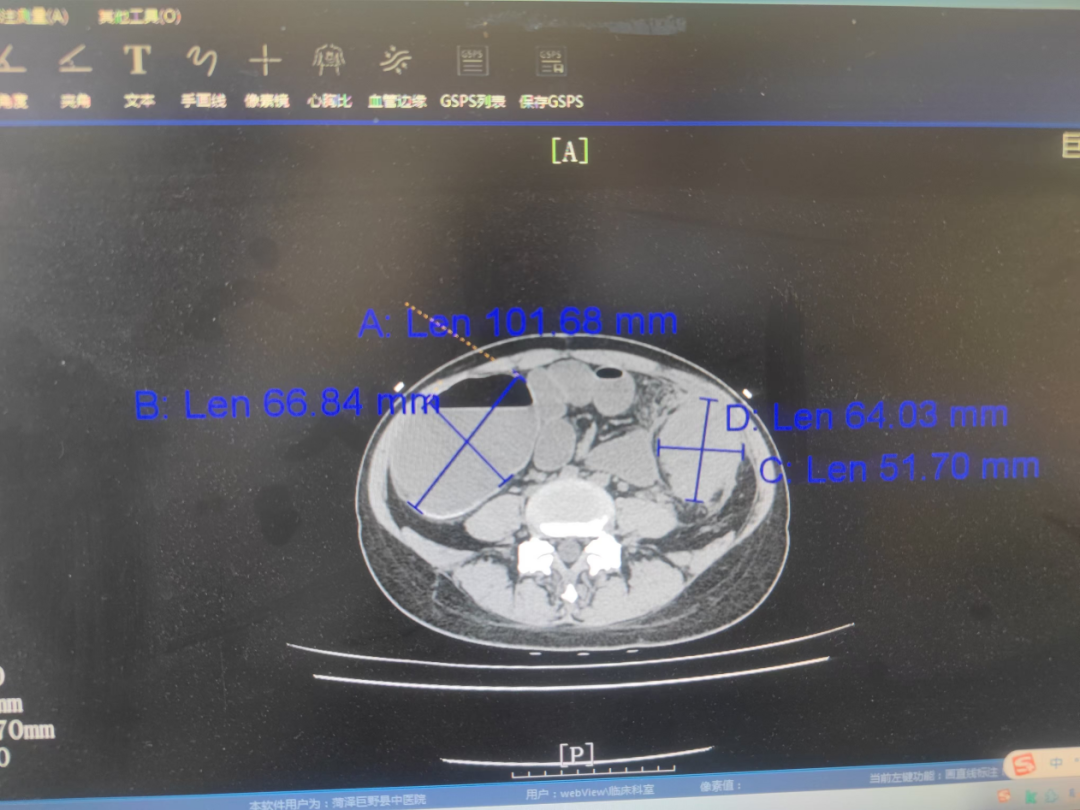

新春伊始,我院外一科收治了一位急性腹痛肠梗阻患者,经检查,在患者左下腹触及质硬巨大包块,直径超10厘米!!腹部CT显示降结肠肠壁明显增厚,肠腔结构不清,近端升结肠和横结肠明显扩张,肠壁变薄。外一科赵加固主任迅速组织多学科会诊,确诊为左半结肠肿瘤并发急性结肠梗阻,属于闭襻性肠梗阻,若不及时手术,盲肠随时可能坏死穿孔,危及患者生命